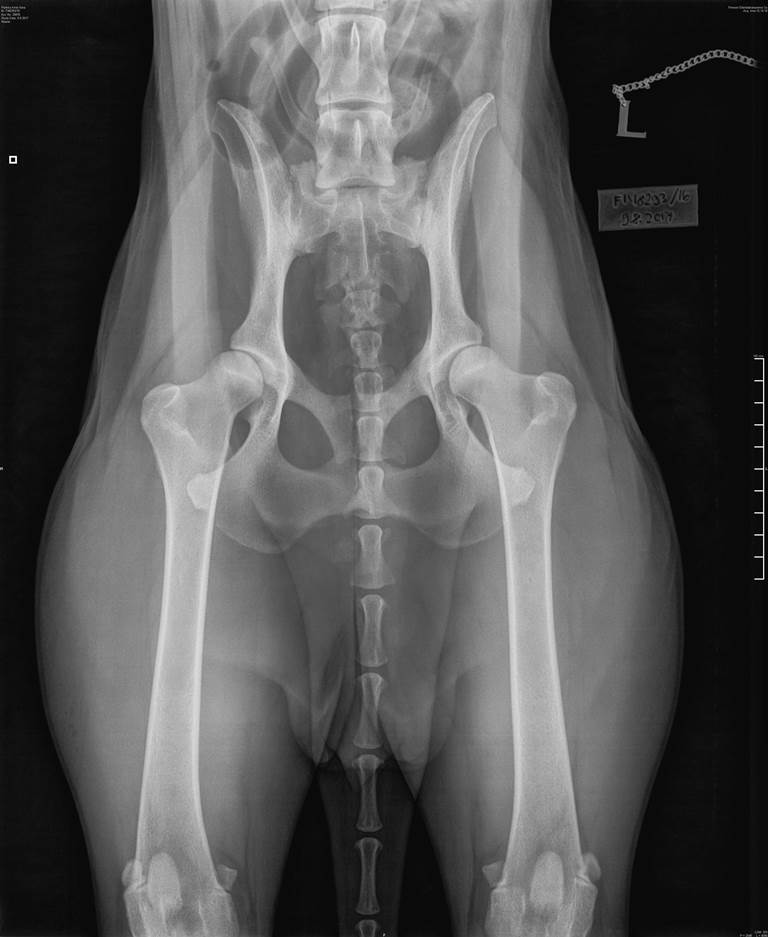

Ilona's hip X-ray